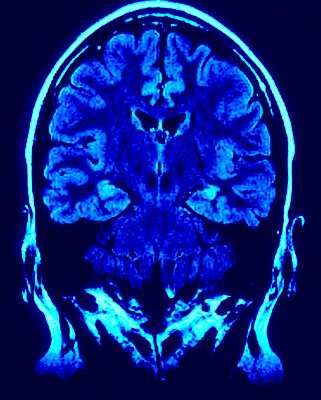

Other, less common symptoms may include depression, difficulty swallowing or chewing, interrupted sleep, skin disorders and difficulty with bodily functions. Parkinson's is a difficult condition to diagnose, as there is currently no definitive blood test or brain scan that accurately identifies Parkinson's disease while ruling out other disorders. Diagnosis is normally based on a neurological evaluation and medical history.